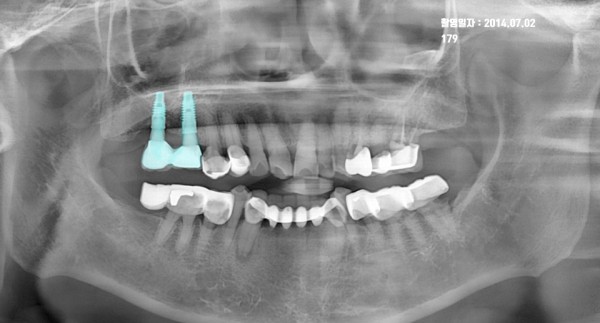

1. 2014년 7월 22일: 임플란트 식립 및 보철 완성 단계

첫 번째 파노라마 사진은 11년 전, 환자분께서 처음 본원에 내원하셔서 상악과 하악에 임플란트 보철을 완성하셨을 때의 모습입니다.

* 치료 포인트: 상실된 치아 부위에 임플란트가 정확한 각도와 깊이로 식립되었습니다.

* 치조골 상태: 임플란트 픽스처(뿌리 부분) 주위로 치조골이 단단하게 결합되어 초기 고정력이 매우 우수한 상태였습니다.

* 광진구 임플란트 전문치과로서, 당시에도 환자분의 구강 구조에 최적화된 맞춤형 보철 설계를 진행하였습니다.